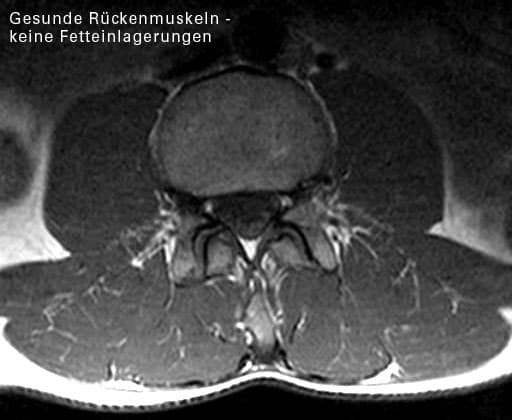

Das abgebildete Kernspin (oberes Bild) zeigt die Muskelverfettung bei einer Patientin, die 5 Jahre lang an therapieresistenten Schmerzen litt. Sie wurde übrigens durch ein gezieltes Krafttraining im MedX-Gerät beschwerdefrei.

Das unten abgebildete Kernspin zeigt gesunde Rückenstrecker. Die fettige Degeneration der Rückenstrecker bei der Patientin ist in der Tat ein krasser Fall. Etwa 60% des Muskelquerschnittes der Patientin ist verfettet. Hier ist nicht mehr viel Kraft da, welche die WS stabilisieren kann.

Die abgebildete Verfettung ist sicher ein Extremfall. Nicht jedes Kernspin sieht so aus. Aber Extremfälle schärfen das Verständnis für das Prinzip:

Schwache Muskeln – fehlende Stabilität – Schmerzen